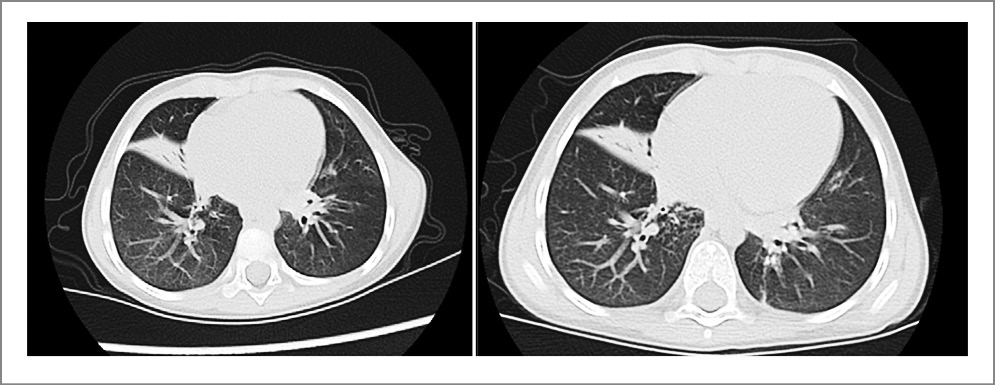

Возраст пациентов в данной группе составил от 9 до 15 лет (медиана 11,5 года). У 2 пациентов с первичной цилиарной дискинезией отмечалось увеличение частоты обострений хронического бронхита в год после перенесенной НКИ (в среднем с 2,8 до 3 раз в год). Как минимум один персистирующий симптом COVID-19 отмечался у 4 (25%) детей через 1 год после острой фазы инфекции. Наиболее часто отмечаемыми стойкими симптомами через 1 год после COVID-19 были снижение физической активности (50%), усталость (37,5%), оговорки при разговоре (25%), трудности с концентрацией (25%). У 1 пациента с первичной цилиарной дискинезией (девочка, 12 лет) отмечались отрицательная динамика КТ ОГК в виде нарастания явлений мукостаза и бронхитических изменений и ухудшение показателей ФВД в виде снижения ОФВ1 с 40 до 25%Д через 1 год после перенесенной НКИ (рис. 1).

Рис. 1. КТ-динамика пациентки с первичной цилиарной дискинезией до и через 1 год после СOVID-19.